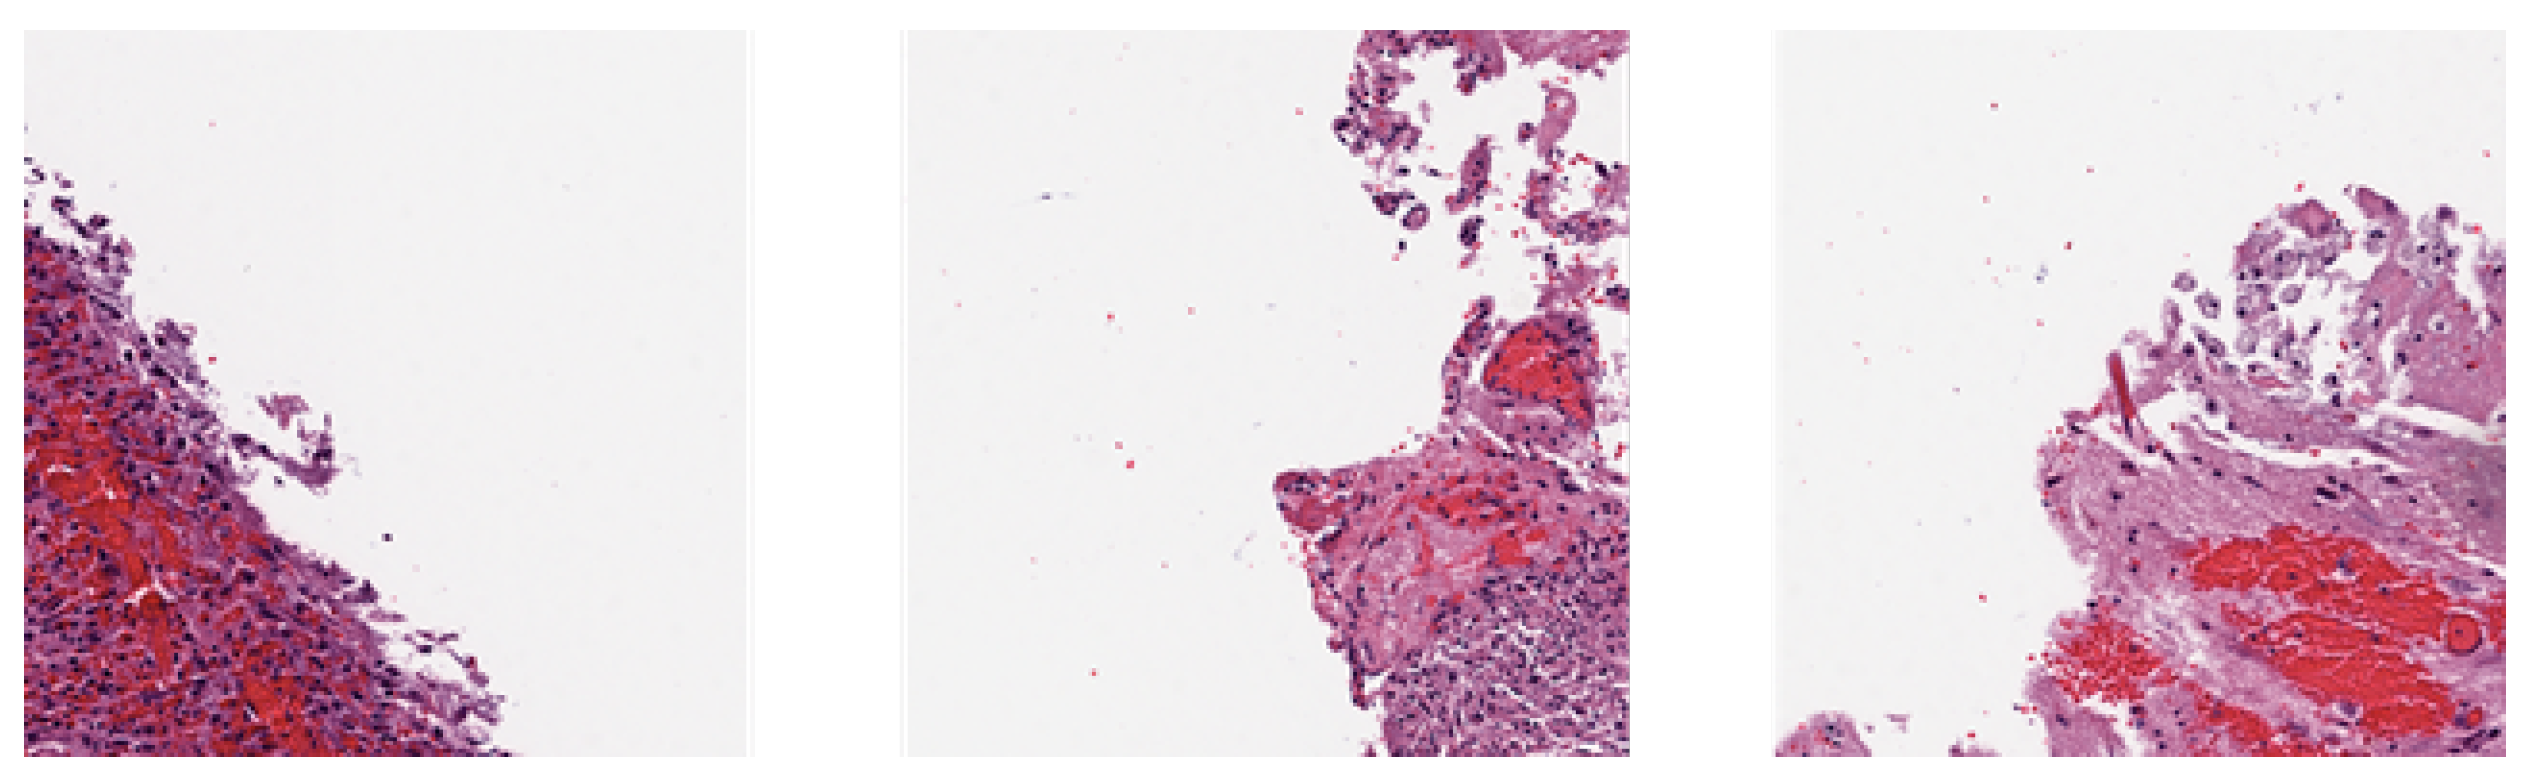

3.2.1. Blank Patches Removal

In medical imaging, WSIs often contain extensive blank regions that do not contribute to model learning. We applied a serie of morphological operations (dilation with kernel (3, 3), closing with kernel (20, 20), and opening with kernel (15, 15)) on masks generated by converting RGB tissue images to HSV color space and segmenting ranges of HSV values above (156, 43, 46) to emphasize regions with tissue. Patches that had 0.5 or less tissue coverage ratio were filtered away. Examples are shown in Figure 2.

Figure 2. These patches with less than 0.5 tissue coverage ratio were removed.